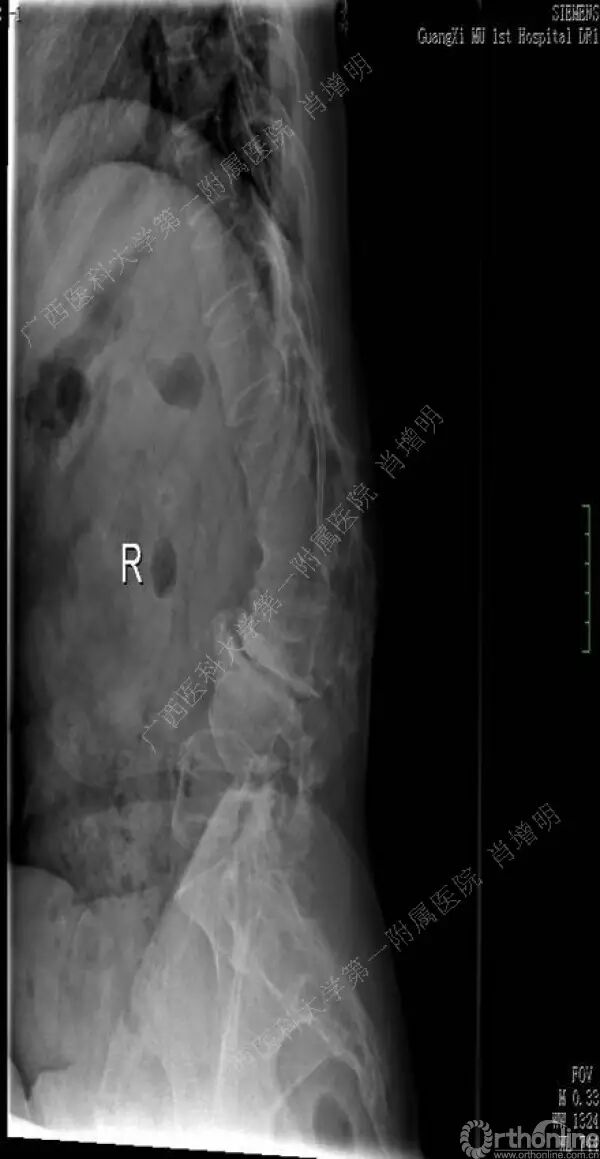

退变性脊柱侧凸是由于椎间盘退变后继发小关节退变,椎管和神经根管容积变化以及脊柱失稳,畸形等病理改变,以疼痛和神经压迫症状为主要表现的常见疾病。

退变性脊柱侧凸多发于50岁以上的中老年群体,是现代常见的老年疾病。多年来,针对该病的临床研究一直没有停步,广西医科大学第一附属医院肖增明教授细致地介绍了该病的诊疗进展。